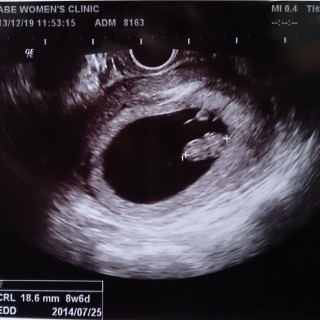

最終生理から計算すると8週ちょうどくらいだったのですが、大きさから8週6日に修正されました。 ずいぶん早くからつわりがあり、まだまだ辛いです。3人目ですが一番つわりがキツイかもしれません。

40歳、初産。ちゃんと人の形になってきて、可愛さ倍増^^ 大きさは19.8ミリ。心拍は1分間に174回。 胸はどんどん張っているけど、2週間前より悪阻もだいぶ治まって、お腹にベビーがいる身体に慣れてきたのかな?

9W3Dだと思っていたのですが、8W6Dでした。手足も見えて、18.5ミリ。今回やっと予定日が分かり、母子手帳も貰えます。ほぼ9週なので、9週の壁を越えられるか不安で仕方ありませんでした。次は仕事の予定が合わず、3週間後。心配ばかりしてないで、強い気持ちで待てるようになろうと思います。

エコーを見る寸前までドキドキでしたが、元気に心臓が動いていました(*^^*)

8w6dで、18.6mmです♪

大きさ的にも順調とのことで、ホッとしました☆